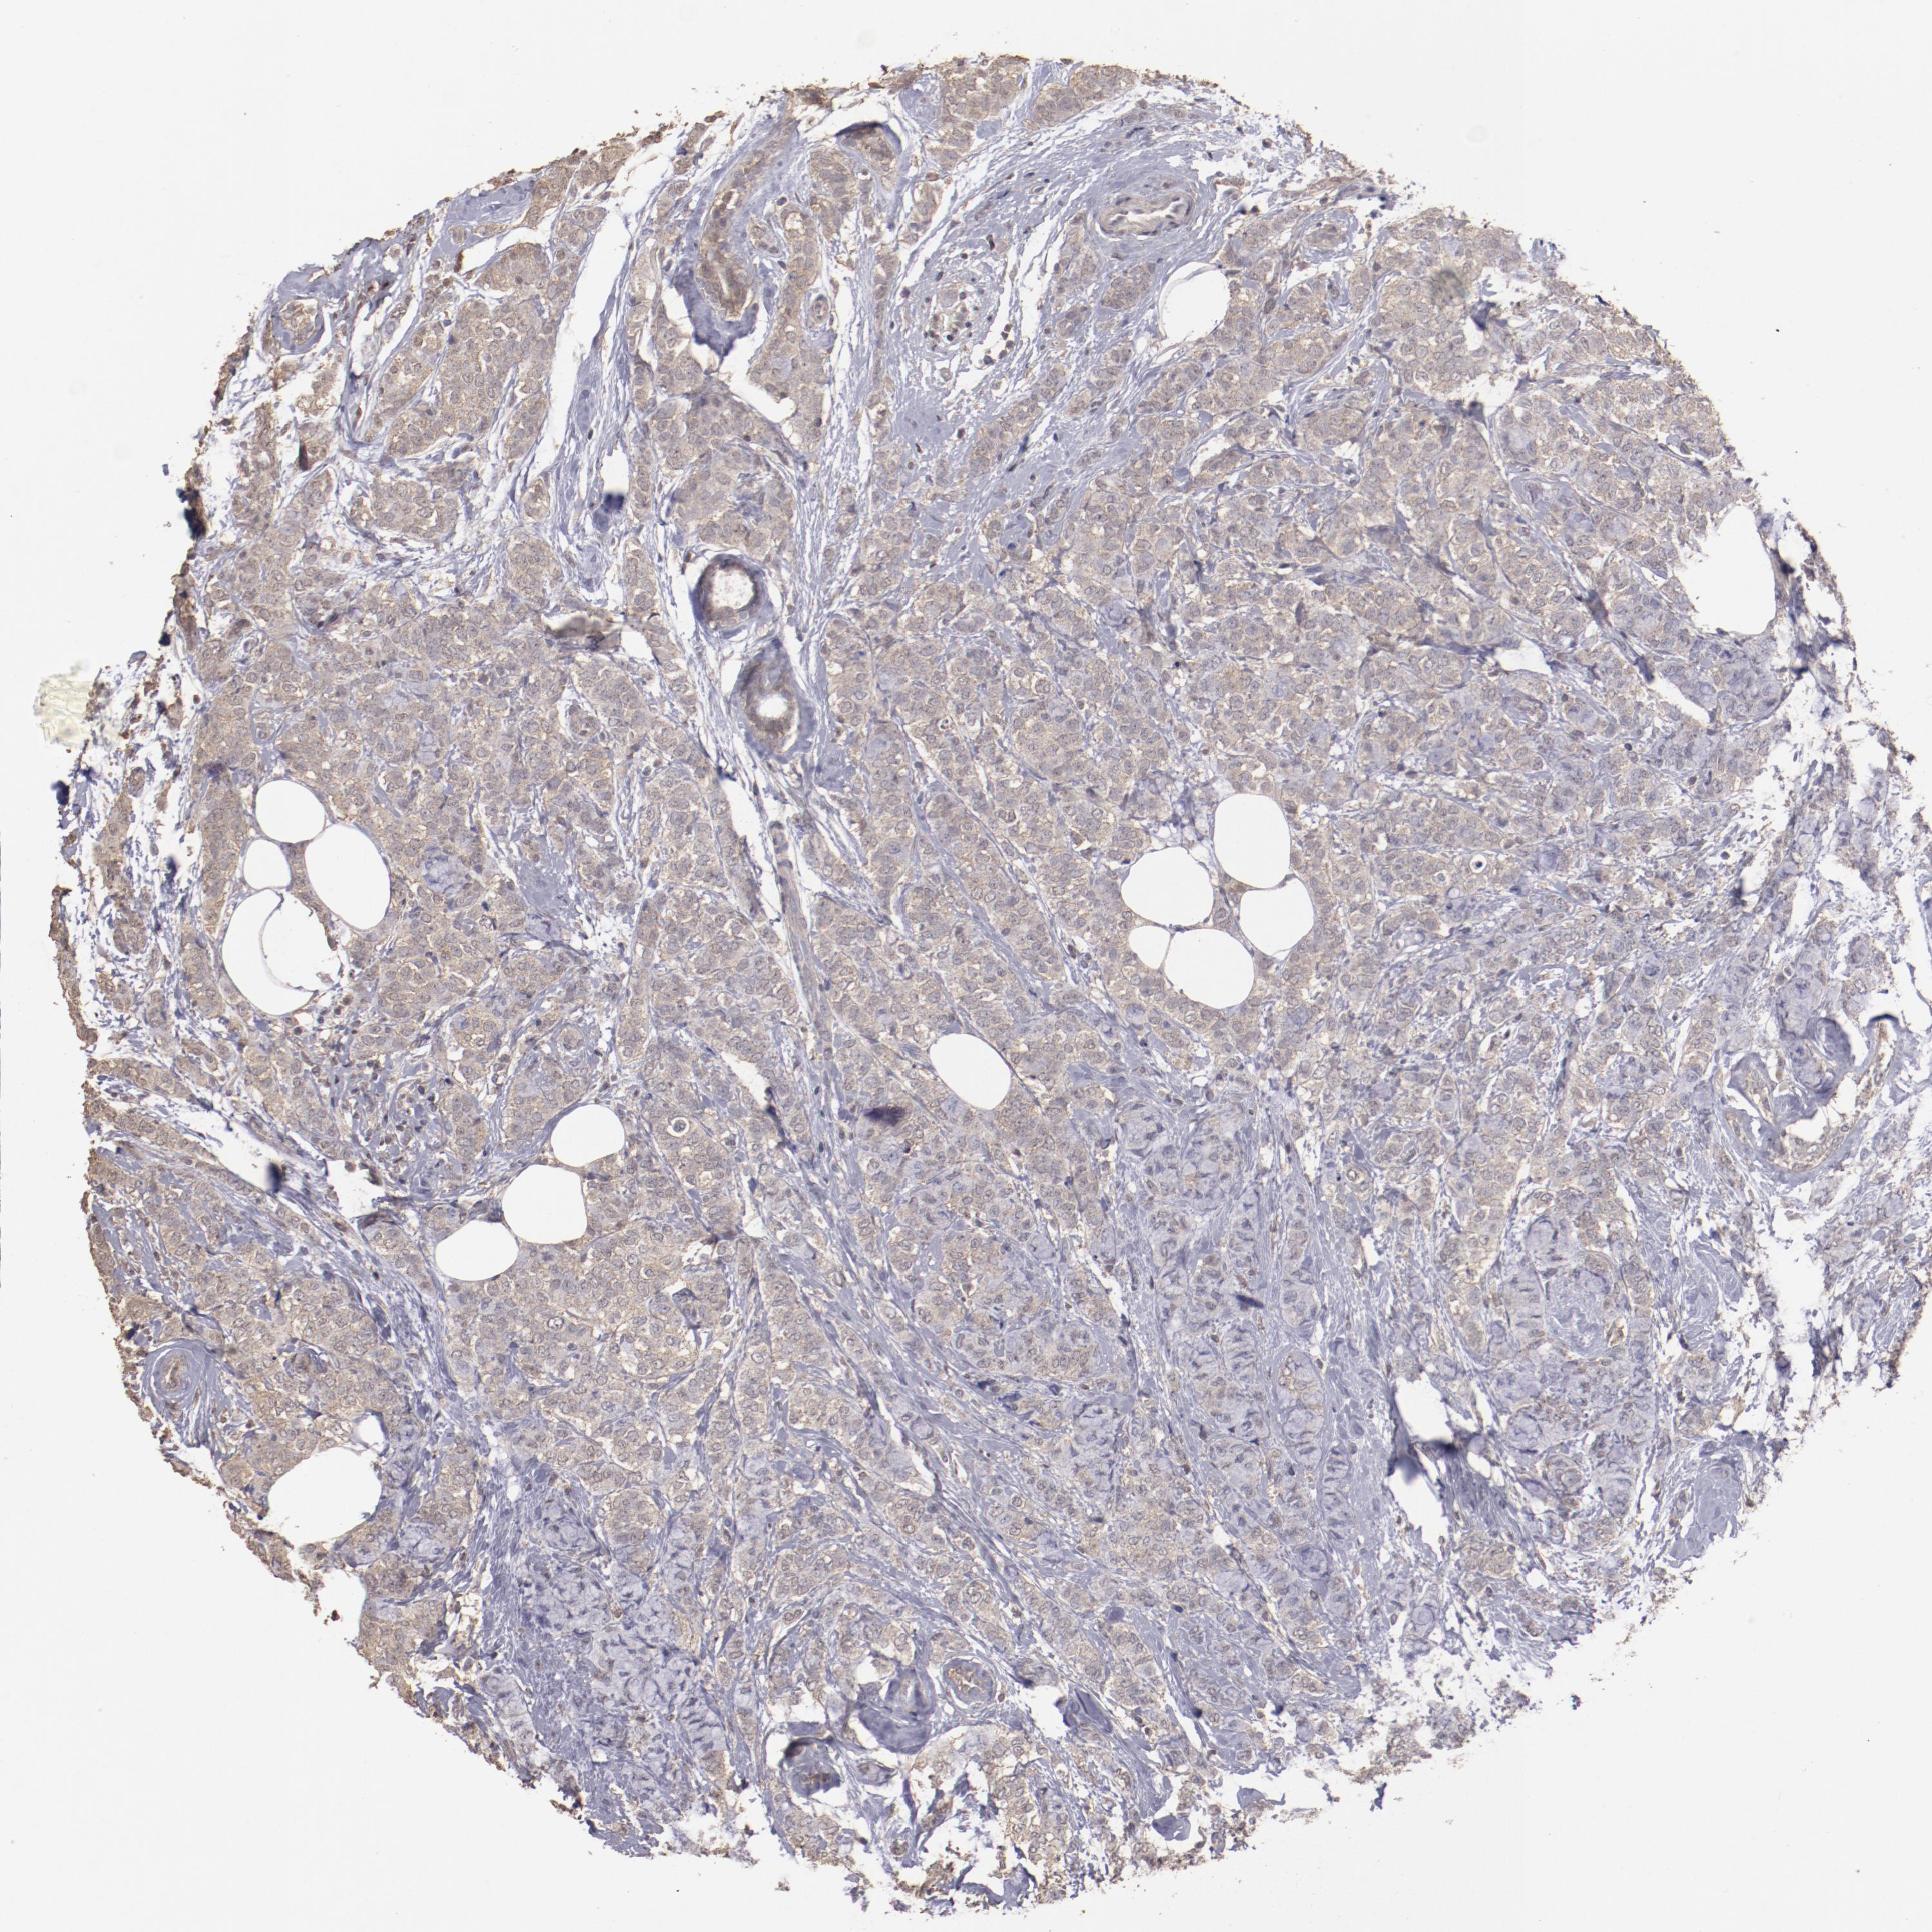

CANCER BREAST CANCER Show tissue menu

BRCA TCGA BRCA VALIDATION PROTEIN EXPRESSION